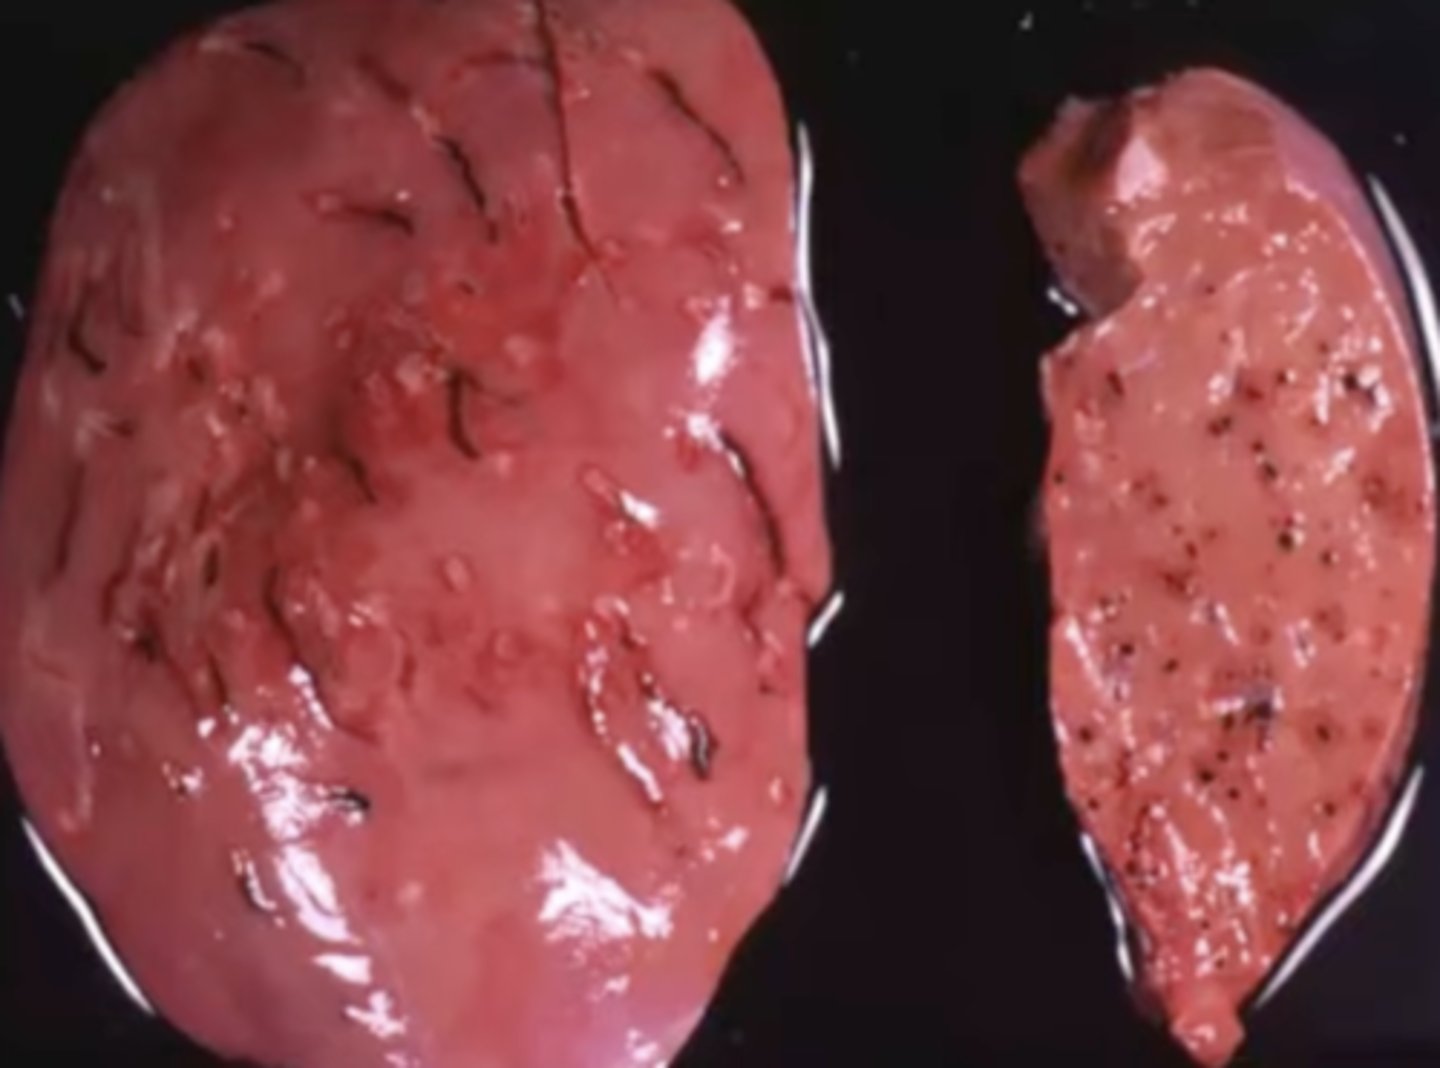

spleen, diffuse enlargement, rounded edges, mottled red color

splenomegaly - splenic lymphoma

Describe this lesion + diagnosis